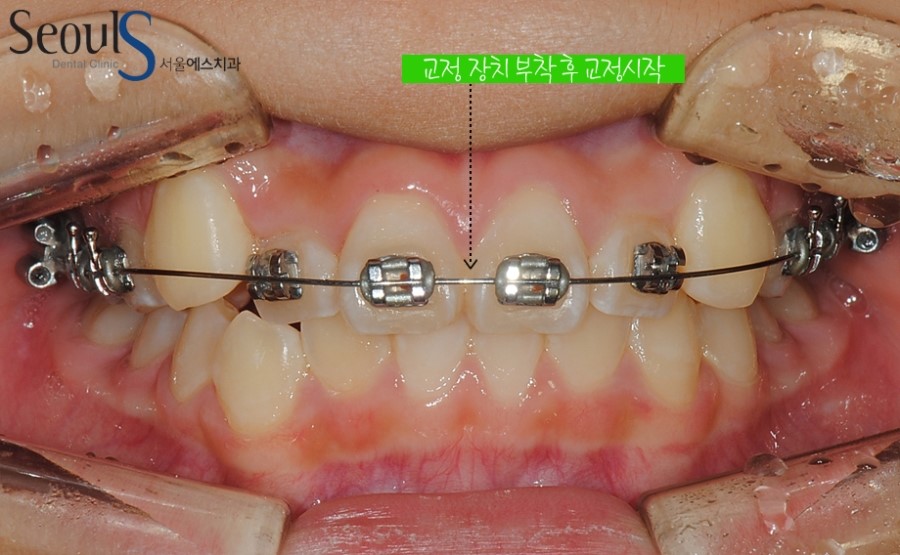

진단 후 장치를 부착해 치아를 서서히 이동시켜 가지런한 치아로 교정하게 됩니다

ex_orth_parkyekyoung (7)교정 장치를 부착해 치아를 가지런하게 이동시키고 있는 모습입니다